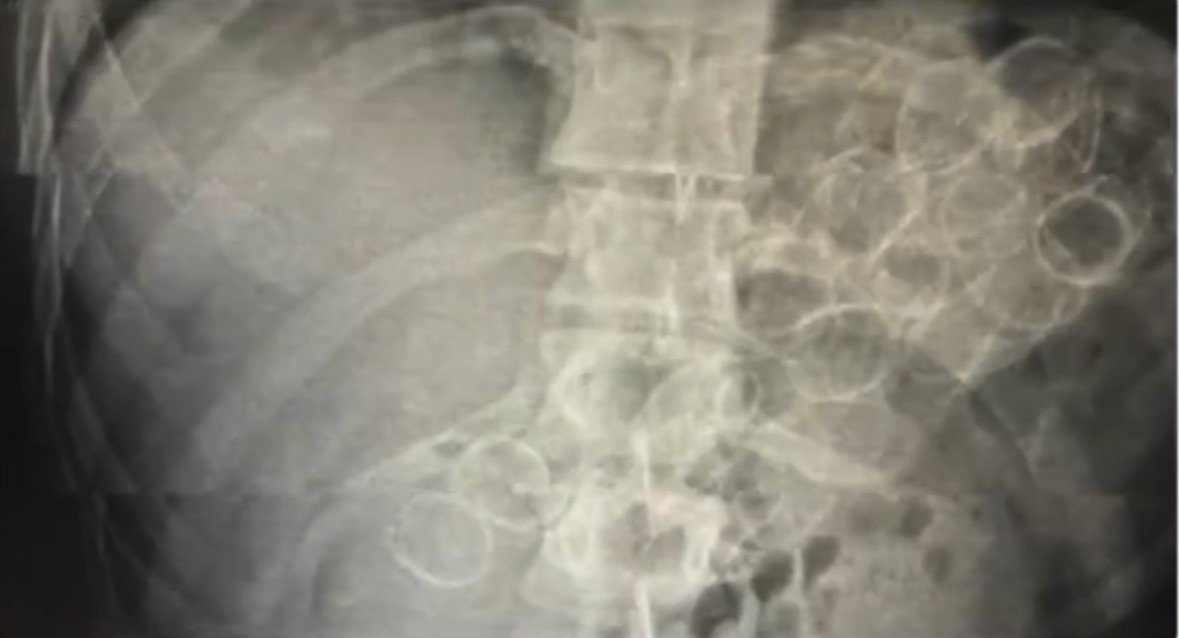

Bingöl İl Emniyet Müdürlüğü Narkotik Suçlarla Mücadele Şube Müdürlüğü ekiplerince yürütülen çalışmalar neticesinde, “Uyuşturucu veya Uyarıcı Madde Ticareti” suçu kapsamında 3 şahsın “yutma ve tıkma” yöntemiyle mide ve bağırsaklarında yüklü miktarda uyuşturucu madde taşıyarak kente getirdiği belirlendi. Ekipler tarafından yakalanan şüphelilerin hastanede yapılan tedavileri sonucunda, toplam 75 kapsül halinde 775 gram metamfetamin maddesi ele geçirildi.